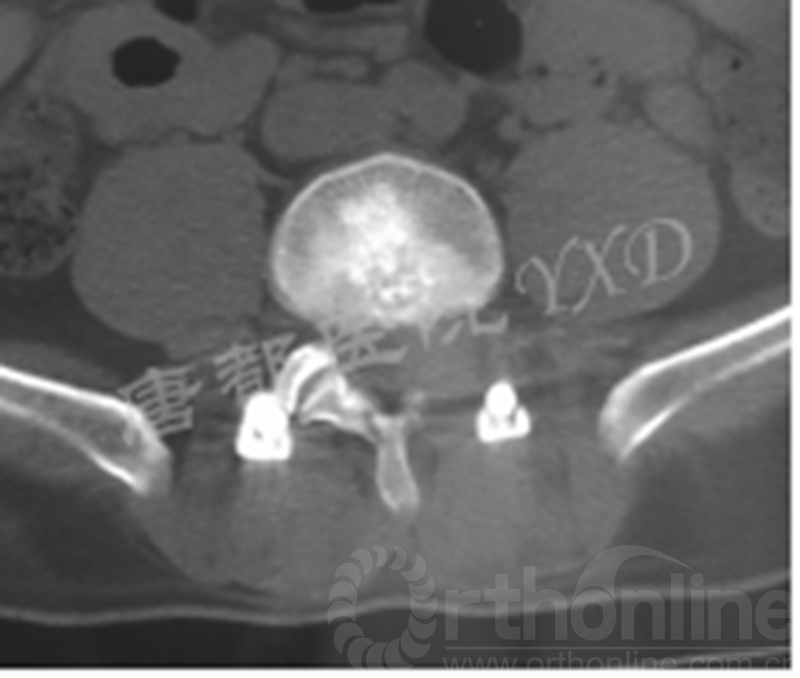

影像学检查:

诊断:腰椎间盘突出症术后复发

手术方案:显微镜辅助MI-TLIF腰椎翻修术